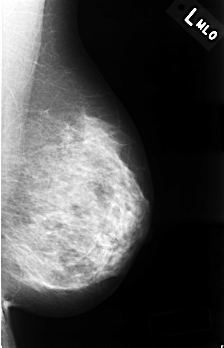

C_0334_1.LEFT_MLO

LEFT_MLO LINES 4512 PIXELS_PER_LINE 2904 BITS_PER_PIXEL 12 RESOLUTION 50 NON_OVERLAY